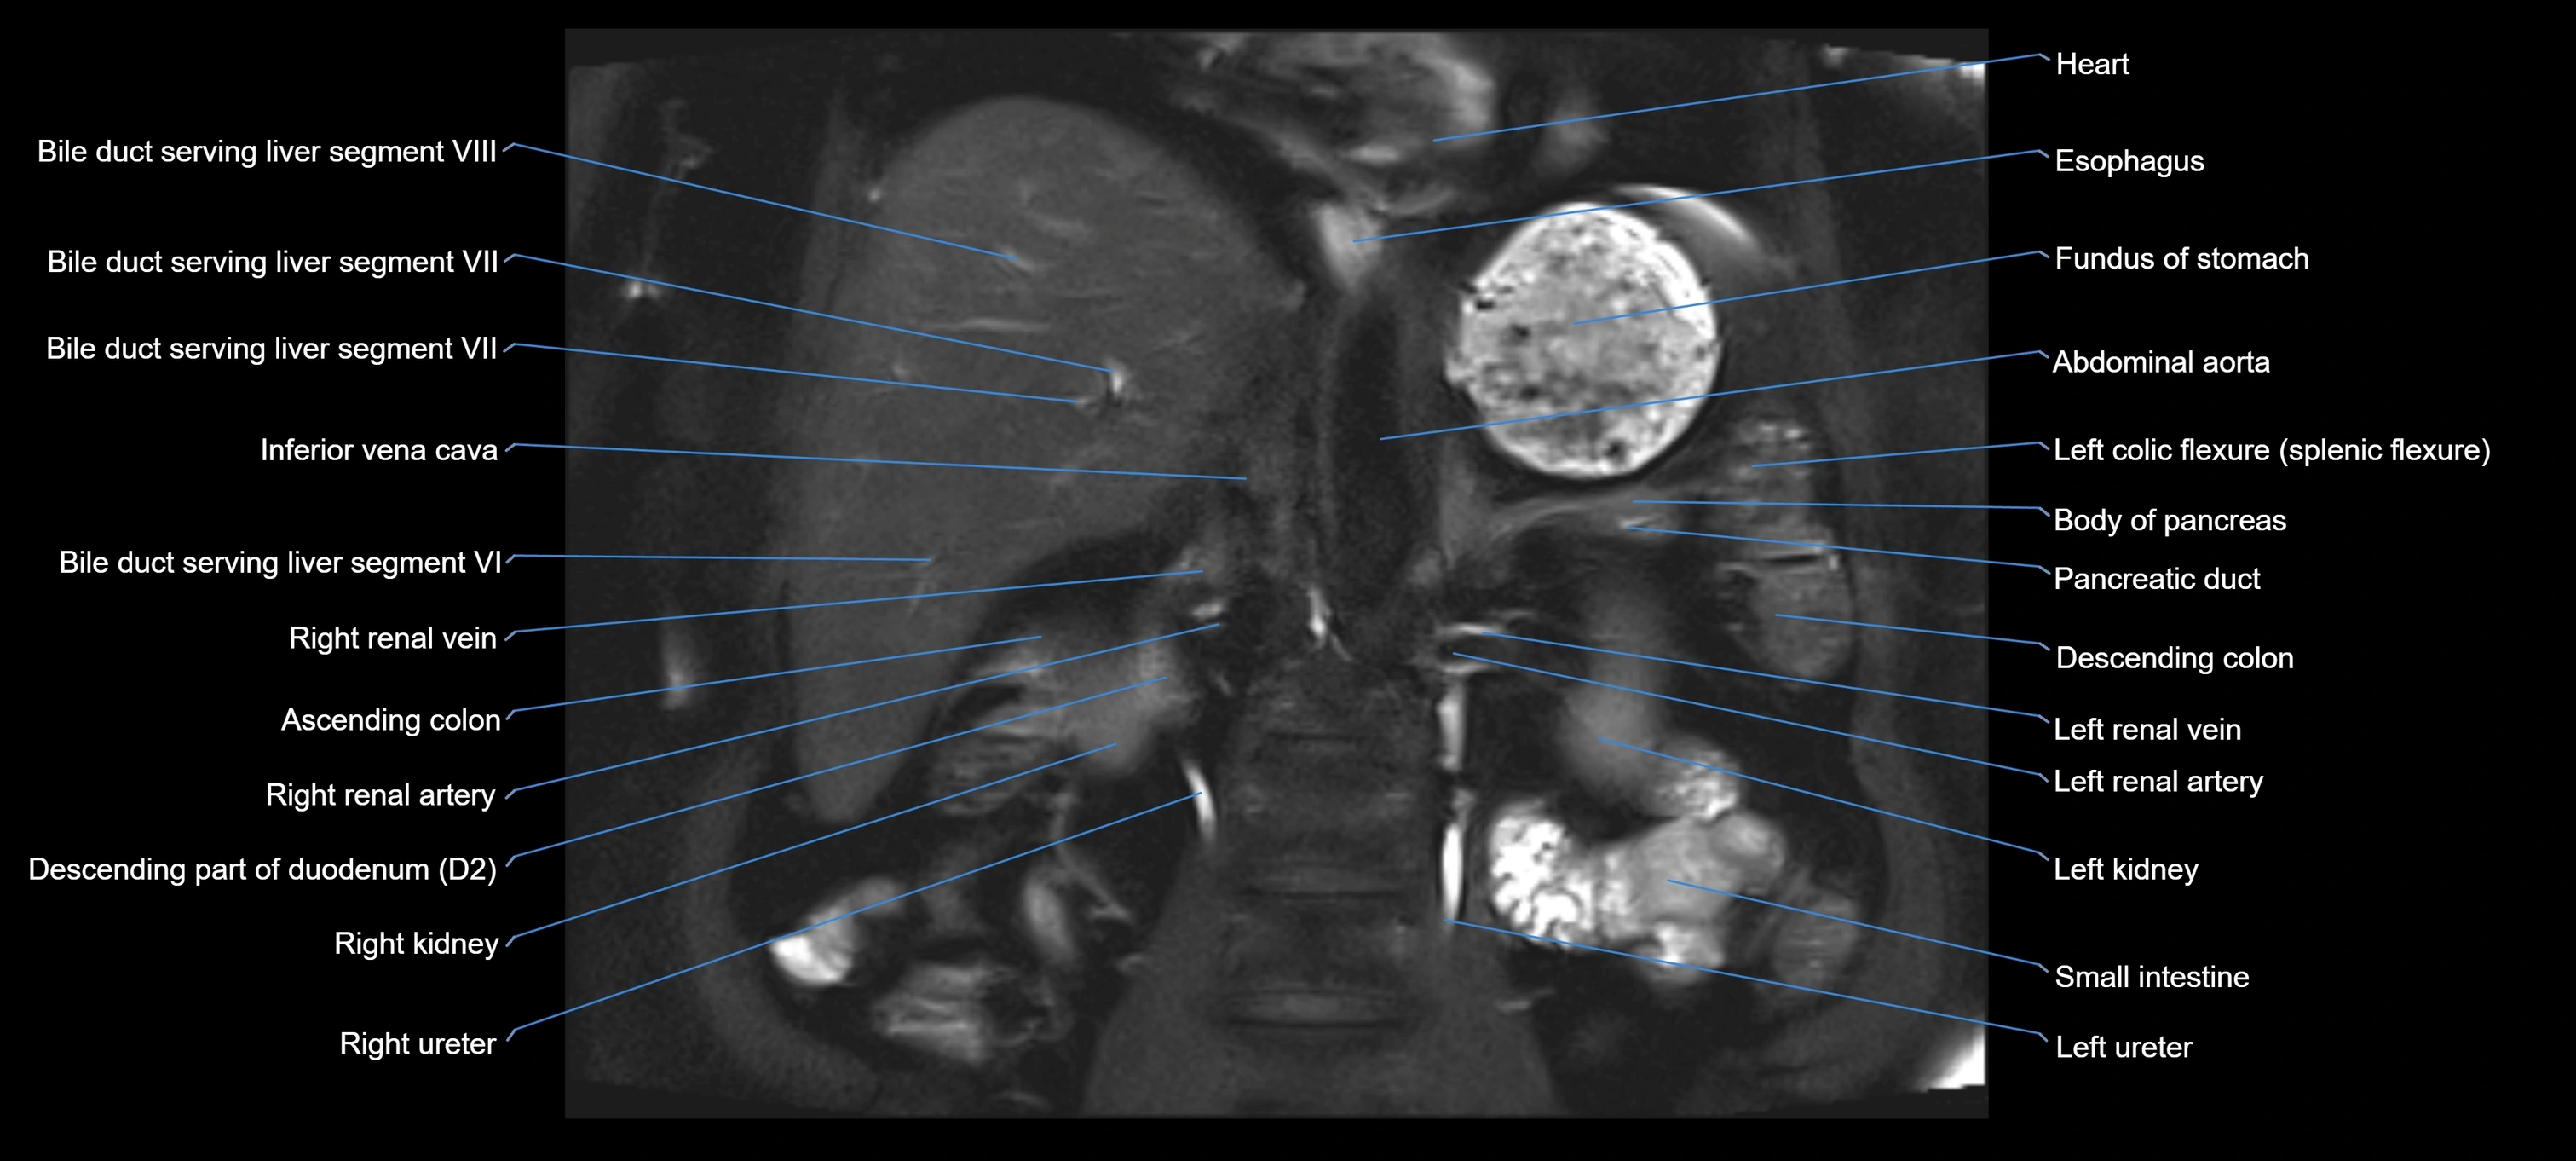

MRI image

image